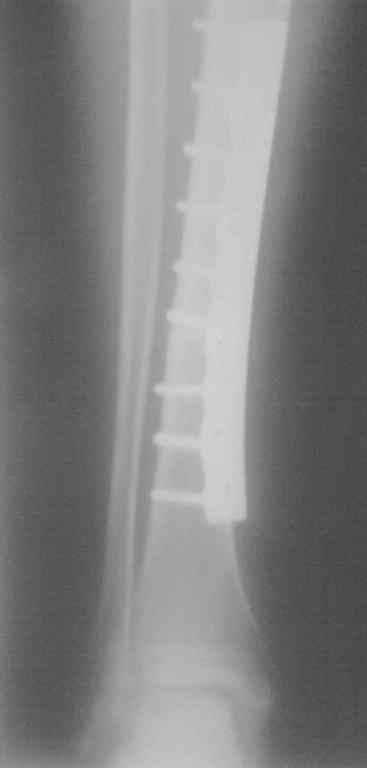

Обследование:на R-грамме костей правой голени в 2-х проекциях-состояние после остеосинтеза накостной пластиной больешеберцовой кости, соотношение костных отломков удовлетворительное. В в/з диафиза периостальная реакция на протяжении 10,0 см.

Уважаемый коллега, к сожалентю по данной Р-грамме правильнл оценить ситуацию не представляется возможныи.

ИМХО. Необходимы Р-граммы в 2-х проекциях желательно более высокого качества. Судя по описанию вы имеете дело с послеопераицонным осложнением. Вариантов лечения несколько и их выбор в значительной степени определяется в основном стабильностью или нестабильностью остеосинтеза и наличием или остсутствием признаков консолидации. Этиотропное лечение скорее всего не будет проблемой т.к. меется MSSА.